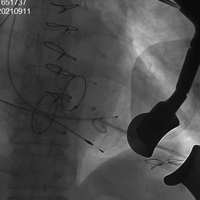

病例一(经右心房三尖瓣瓣中瓣)

患者女性,68岁,既往行三尖瓣生物瓣置换术,二尖瓣机械瓣置换术,三尖瓣位置入佰仁思29#瓣膜一枚。STS评分9.69%,属于外科换瓣手术高风险患者。术前心脏超声示原三尖瓣生物瓣中量反流。术前详尽评估,经股静脉路入同轴性不理想,且右颈静脉既往手术存在瘢痕狭窄,故术中选择腋下小切口途径,通过右心房穿刺植入27# Renato球扩式瓣中瓣,释放成功后瓣膜功能良好,无明显瓣中及瓣周反流,平均跨瓣压差0.5mmHg。

瓣膜释放